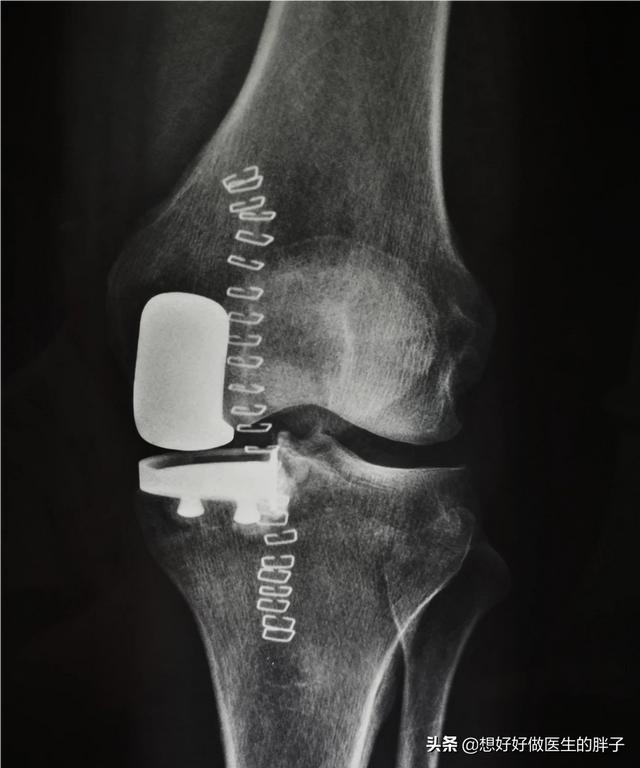

fortgeschrittenes Krankheitsstadiumdie sich in der Regel als stärkere Knieschmerzen äußern, wobei bei einigen Patienten erhebliche Defizite in der Beugung und Streckung der Gelenke auftreten, wenn die Erkrankung schwer genug ist, um zu erscheinenRuheschmerz und nächtlicher SchmerzEs ist ein Zeichen dafür, dass der Zustand des Patienten einen Punkt erreicht hat, an dem ein chirurgischer Eingriff notwendig ist, um ihn zu beheben. Diese Art der Operation nennen wirKniegelenkersatzViele Menschen denken, dass der gesamte Kniegelenkknochen entfernt und durch eine Prothese ersetzt wird. Dieses Verständnis ist falsch, denn bei der Kniegelenkersatzoperation wird die gebrochene Knorpeloberfläche entfernt und durch eine Metalloberfläche ersetzt, weshalb sie auch Kniegelenkoberflächenersatzoperation genannt wird. Und mit dem Fortschritt der heutigen Technologie, um das Gelenk des Patienten besser zu schützen und zu erhalten, wird nun auch damit begonnen, folgende Operationen durchzuführenTeilarthroplastik。

Wenn sich Patienten einer chirurgischen Behandlung zum Gelenkersatz unterziehen, führt eine gute systematische Rehabilitationsübung zu sehr guten postoperativen Ergebnissen.